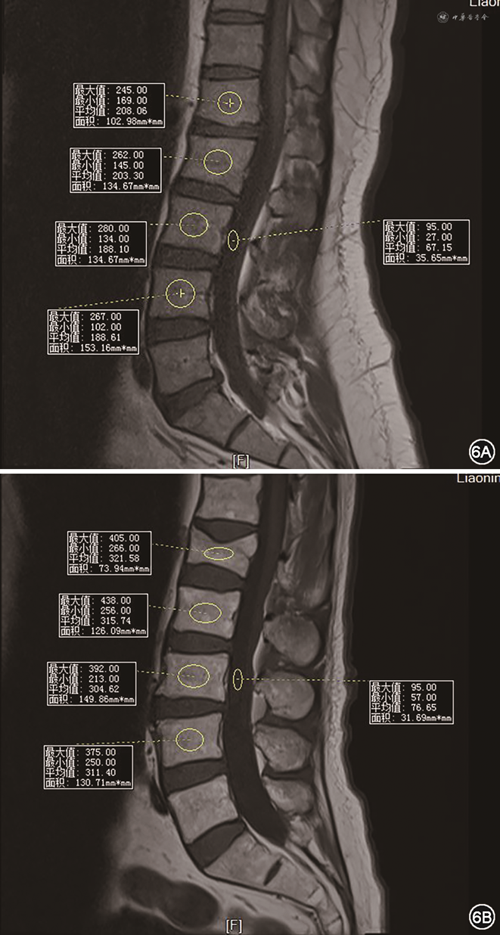

9.MRI:基于腰椎MRI T1加权(T1WI)像,通过测量椎体内部感兴趣区的信号强度来评估椎体内部脂肪浸润程度以及椎体骨的质量(vertebral bone quality,VBQ)[45],有助于评估骨质疏松情况。采用腰1~4椎体感兴趣区内平均信号强度(SIL1~L4)除以脑脊液的信号强度(SICSF),得出 VBQ 评分,研究显示VBQ评分与DXA的T值呈负相关[45](图6),该研究显示较高的VBQ评分与骨量减少/骨质疏松症显著相关,预测准确性为81%。有学者将VBQ临界值设置为2.93,此时诊断低BMD的敏感度为77.25%、特异度为70%[46]。临床上MRI用于脊柱脆性骨折的诊断、X线和CT不能明确诊断的隐性骨折、背部疼痛诱导试验阳性患者,以及骨质疏松性骨折、骨肿瘤及其他疾病引起的病理性骨折的鉴别[47]。其优点在于无放射性损害、软组织对比度高、可显示骨髓的早期变化[48, 49]、不受观察者影响等[50]。但是其成本较高、设备使用的有限性和复杂性较高,同时该评分仅能区分骨量正常与骨量减少或骨质疏松,尚缺乏采用MRI进行骨量减少和骨质疏松划定的研究,缺乏二者的量化区分标准,尚不能用于治疗方案的选择及疗效判定。